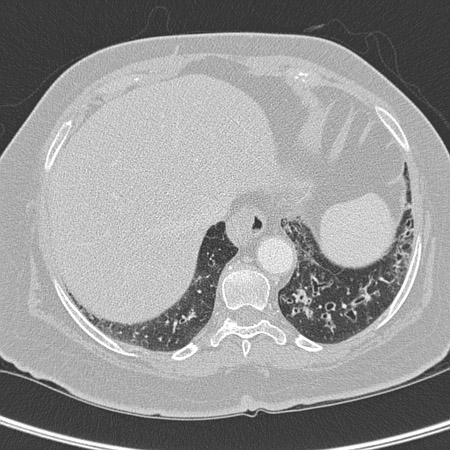

• High-resolution CT imaging of the chest to look for bronchiectasis (which does not always promote a productive cough), foreign body aspiration, pulmonary fibrosis, or other structural lung disease (which may not show well on chest x-ray). Chronic suppurative lung disease is diagnosed in patients with clinical symptoms of bronchiectasis but no radiographic evidence of bronchiectasis.[50] CT imaging may also indicate the presence of an aortic aneurysm or Zenker’s diverticulum. The diagnostic yield of the CT scan of the chest in a patient with chronic cough and normal chest x-ray is expected to be low.[3][Evidence C] There is no high-quality evidence to support the use of chest CT in the initial evaluation of patients presenting with chronic cough.[38]

[Figure caption and citation for the preceding image starts]: Chest CT with presence of signet ring on left in a patient with bronchiectasisFrom the personal collection of Dr S.M. Bhorade, University of Chicago Medical Center [Citation ends].com.bmj.content.model.assessment.Caption@769db40d[Figure caption and citation for the preceding image starts]: Chest CT with dilated and thickened airways and peripheral tree-in-bud pattern in a patient with bronchiectasisFrom the personal collection of Dr S.M. Bhorade, University of Chicago Medical Center; used with permission [Citation ends].com.bmj.content.model.assessment.Caption@5d8c3fb7[Figure caption and citation for the preceding image starts]: Chest CT showing idiopathic pulmonary fibrosisFrom the personal collection of Dr J.C. Munson, Center for Clinical Epidemiology and Biostatistics, University of Pennsylvania School of Medicine [Citation ends].com.bmj.content.model.assessment.Caption@43159570[Figure caption and citation for the preceding image starts]: Chest CT of a patient with amiodarone pulmonary toxicity, showing asymmetrical opacities with a peripheral distributionFrom the personal collection of Dr A. Pataka and Professor P. Argyropoulou, Aristotle University, Thessaloniki, Greece [Citation ends].com.bmj.content.model.assessment.Caption@33fbbbbd[Figure caption and citation for the preceding image starts]: CT of the chest with intravenous contrast material showing complete left lower lobe collapse with a radiopaque object within the left lower main bronchus surrounded by a halo of airBMJ Case Reports 2008 (doi:10.1136/bcr.06.2008.0013). Copyright 2008 BMJ Publishing Group Ltd [Citation ends].com.bmj.content.model.assessment.Caption@72dca222[Figure caption and citation for the preceding image starts]: Bronchoscopy image showing a loquat seed completely occluding the bronchus intermediusFrom the personal collection of Dr S. Murgu and Dr H. Colt, University of California at Irvine Medical Center [Citation ends].com.bmj.content.model.assessment.Caption@18215d6d